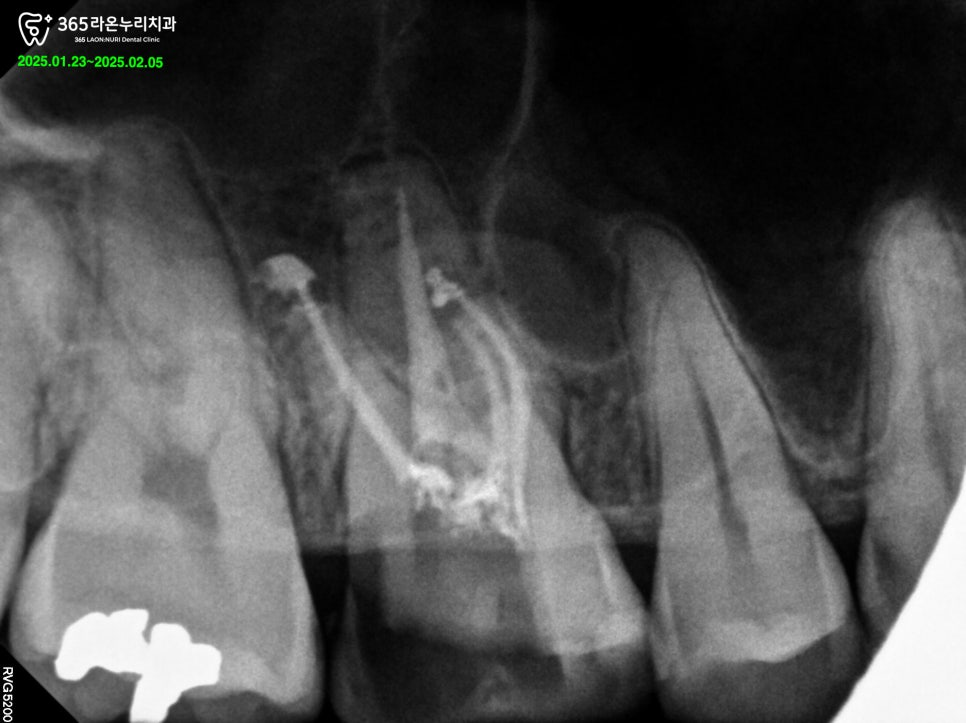

신경치료를 잘하는 치과의사일수록

평균치와 다른 의외의 근관을 찾는 것에

능숙하다는 말이 있습니다.

잘하는 사람한테는 네번째 근관이

더 잘 보인다는 뜻입니다.

숙련도가 높을 수록 이렇게 숨겨진

근관을 잘 찾아내어, 미세한 곳까지

꼼꼼하게 채워줄 수 있습니다.

이런 근관 치료의 불확실함을

잘 해결하려면 그만큼의 많은 임상 경험을

동반할 필요가 있습니다.

세교동 치과 원장의 노련한 임상

기술과 루페 장비를 이용한 신경치료 과정을

꼼꼼하게 진행하여 해당 과정은

잘 마무리 지을 수 있었습니다.

신경치료 이후

치아를 보호할 수 있는 크라운을 씌우기 위한

코어를 만들어 주었습니다.